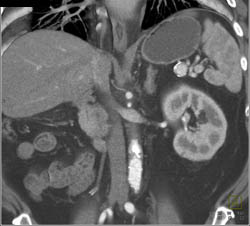

Splenic Hemangioma